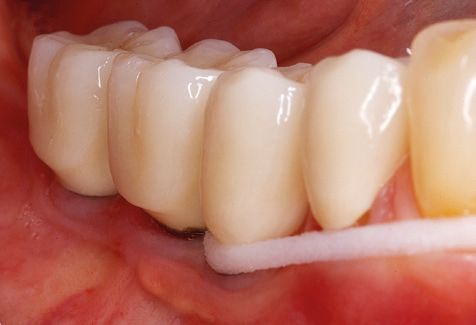

Unerlässlich für die UPT implantat­ prothetisch versorgter Patienten sind natürlich Arbeitsspitzen für die Reini­gung von Implantatoberflächen. Der Implantatreinigungsaufsatz des hier verwendeten Systems zeichnet sich dabei durch eine spitz zulaufende sechskantige konische Form aus. Dieses Design erlaubt ein leichtes atraumatisches Eindringen in die periimplantäre Tasche und zeigt eine gute Reinigungsleistung (Abb. 7).

Abb. 4: Für das Sondieren an dentalen Implantaten sind biegsame, millimeterskalierte Sonden empfehlenswert (z.B. Colorvue Kit PCV11KIT6, Hu-Friedy). – Abb. 5a und b: Eine gerade Arbeitsspitze (1P, W&H Dentalwerk Bürmoos GmbH) ist universell für die Instrumentierung natürlicher Zähne geeignet. – Abb. 6: Für die Bearbeitung schwer zugänglicher Bereiche der Zahn- und Wurzeloberflächen (z.B. Furkationen) bieten sich gebogene Arbeitsspitzen (3Pr/3Pl, W&H Dentalwerk Bürmoos GmbH) an. – Abb. 7: Die spitz zulaufende sechseckige Implantatreinigungsspitze (1I, W&H Dentalwerk Bürmoos GmbH) ermöglicht eine atraumatische und effiziente Reinigung der Kronen- und Abutmentoberflächen. – Abb. 8: Für die manuelle Instrumentierung der Implantatoberflächen sind Titan- oder Carbonküretten geeignet.